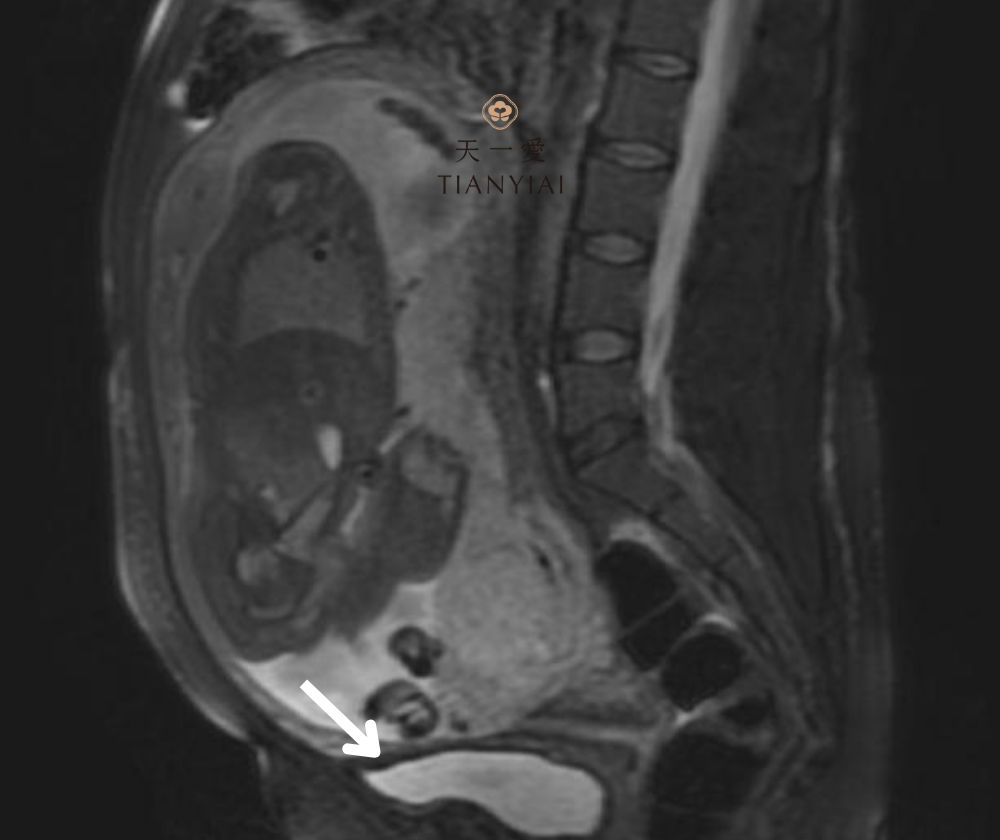

Nhau tiền đạo (hoặc nhau thai tiền đạo) là tình trạng bánh nhau bám bất thường ở phần dưới tử cung, che phủ một phần hoặc toàn bộ cổ tử cung – nơi em bé sẽ đi qua khi sinh thường. Thay vì nằm ở vị trí cao trên thành tử cung như bình thường, bánh nhau lại “đi trước”, chắn ngay lối ra của thai nhi.

5. Chẩn đoán và điều trị nhau tiền đạo

Phương pháp chẩn đoán chính là siêu âm – đặc biệt là siêu âm đầu dò âm đạo (an toàn và chính xác cao). Thường phát hiện vào tuần thứ 18–20 trong lần siêu âm hình thái học thai nhi. Tuy nhiên, chẩn đoán xác định được đưa ra rõ nhất từ tuần thứ 28 trở đi.

Siêu âm cho phép bác sĩ đánh giá chính xác vị trí bánh nhau và mức độ nguy hiểm – từ đó xây dựng kế hoạch theo dõi hoặc can thiệp kịp thời.